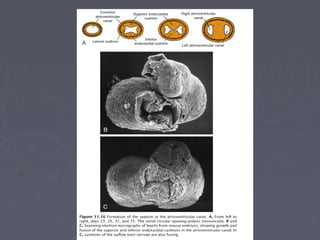

The ventricles position themselves and the great vessels spiral down

to cross the circulation before the truncal septum fuses with the

superior margin of the septal crest.

Inferior to this, the posterior part of the septal crest is heading towards the AV valve,

which itself is dividing into the mitral and tricuspid valves

Four cushions (AVC) have

developed at the A/V junction; the

superior and inferior cushions will

meet to divide the AV orifice (AVO)

into the tricuspid and mitral valves.

The inferior septal crest (VS)

will aim to meet the divided valve

where the cushions fuse.